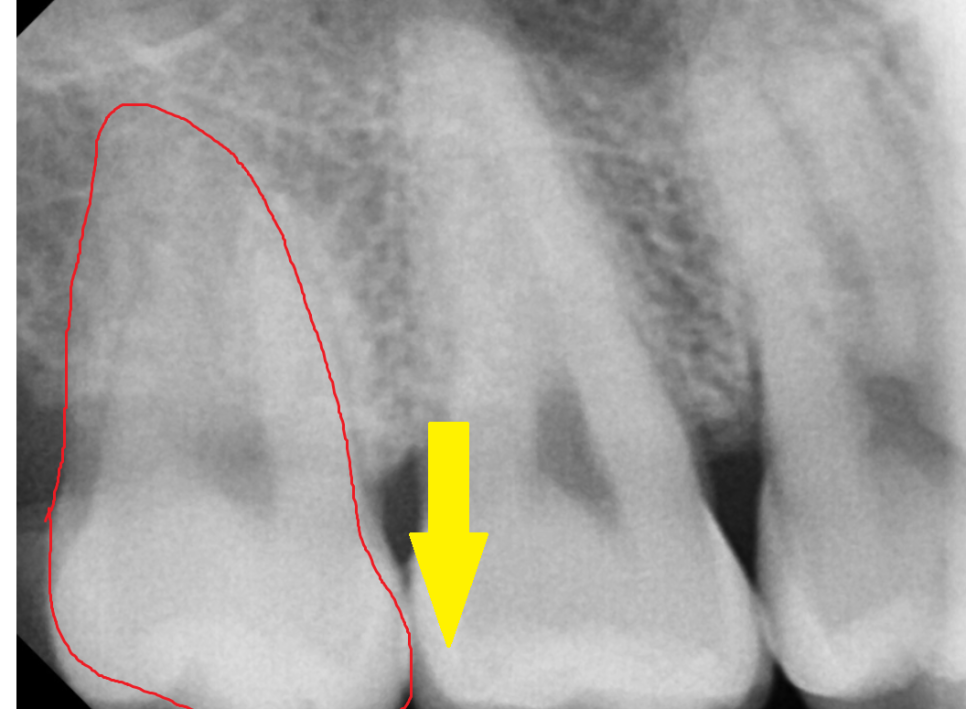

사진 속 4개의 사랑니가 있는데요.

한눈에 보기에도 아래쪽에 위치한 사랑니는

누워있죠~?

누워있고 숨어있는 사랑니는

발치 난이도가 증가하지만

예쁘게 잇몸 밖으로 올라온 사랑니,

윗니 사랑니는 수월하게 뽑을 수 있습니다 .

이렇게 누워서 난 사랑니는

수직으로 뽑을 수가 없기 때문에

쪼개서 뽑아야합니다.

발치 난이도도 올라가고

뼈도 삭제해야해서

발치 후 통증이 심할 수 있습니다.